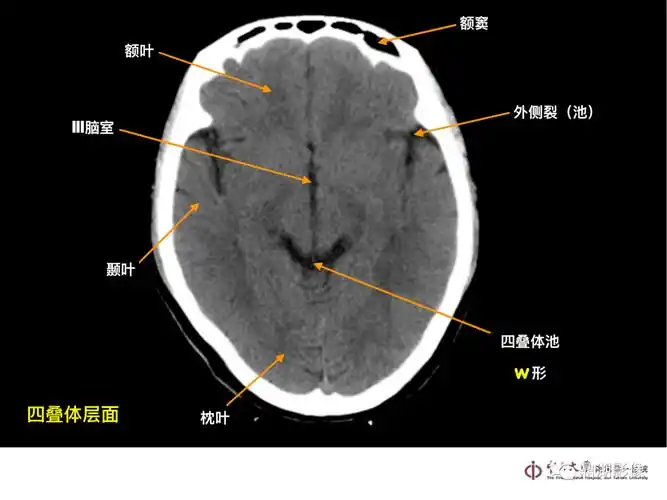

超实用急诊头颅ct3b阅片法